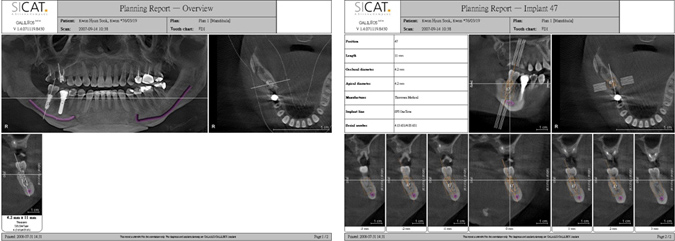

CT成像,可製作成簡報,供患者參考,維護患者自身權益